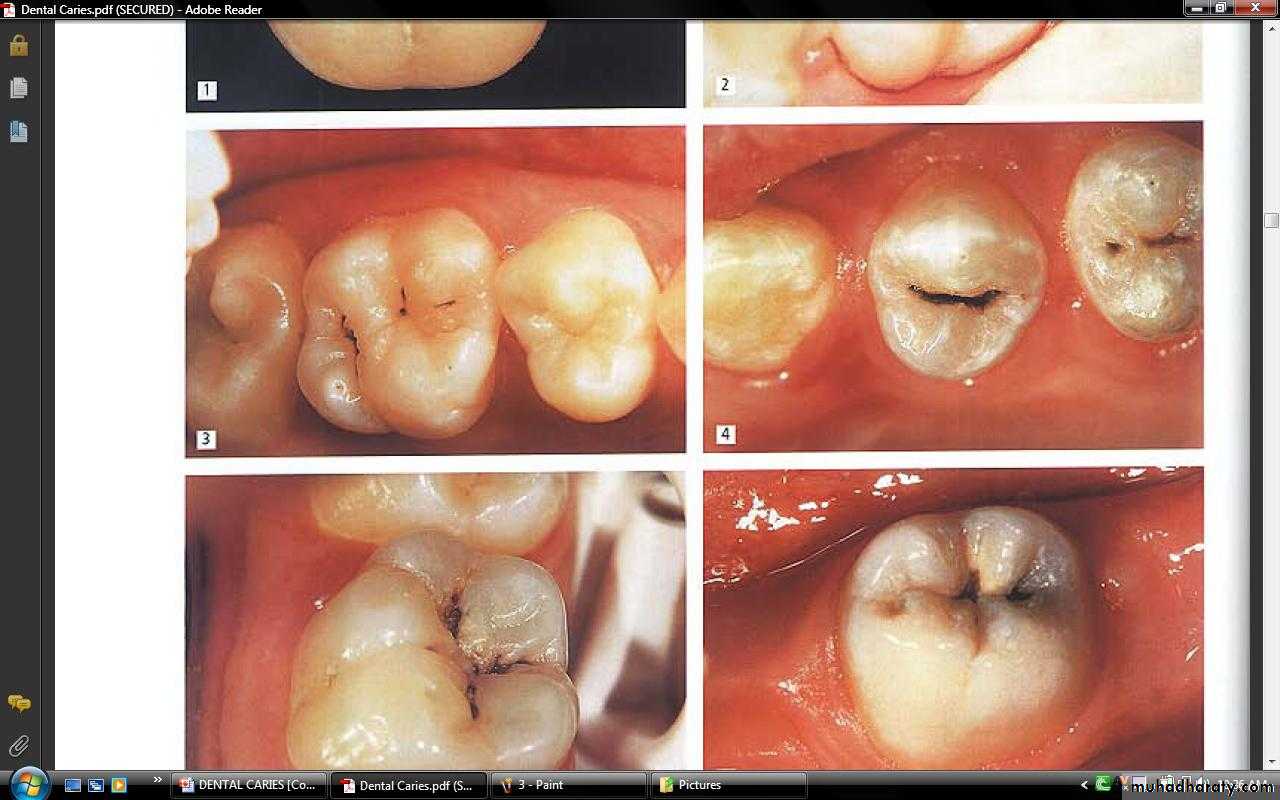

ACUTE DENTAL CARIES

It is that form of caries that follows a rapid clinical course and results in early pulpal involvement by carious process.Predominantly affects children and young adults probably because their dentinal tubules are larger and show no sclerosis.

The point of entry of caries is small even though there is rapid spread of caries at DEJ, producing large internal cavitation.

The small point of opening doesn’t allow the buffering ions of saliva to neutralize acids formed within the cavity.

The affected dentin is usually stained light yellow compared to deep brown / black of chronic caries.

CHRONIC DENTAL CARIES

That type of caries which progresses slowly and involves the pulp much later than acute caries.Most commonly seen in adults.

Opening to the lesion is invariably larger than that of acute caries. As a result, there is lesser food impaction and greater access to saliva.Also, the slow progress of caries allows enough time for dentinal sclerosis and deposition of tertiary dentin in response to irritation.

The carious dentin is stained deep brown

As compared to acute caries there is considerable SURFACE destruction with a shallower cavity and little undermining of there is only enamel, while moderate spread of caries along the DEJ.Pain is NOT a prominent feature here due to the protection provided to the pulp by tertiary dentin formation.